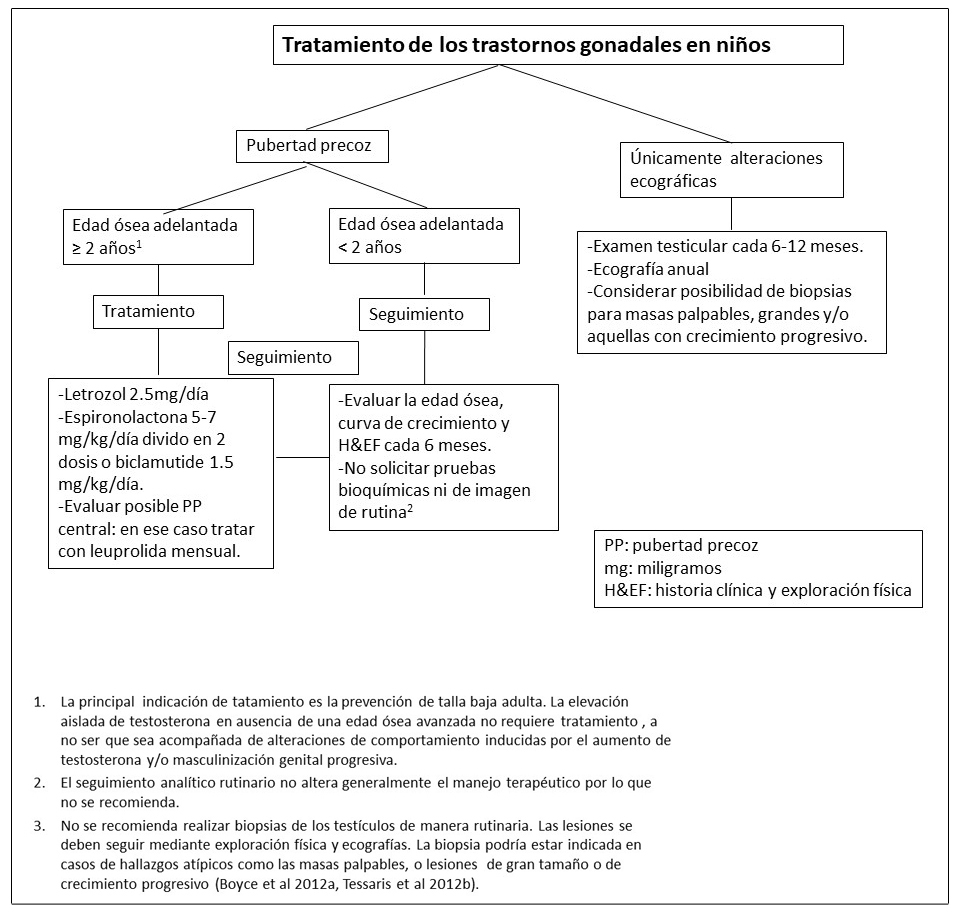

Enfermedad tiroidea.

La afectación de la glándula tiroides es muy frecuente en los pacientes con DF/MAS. Se detectan alteraciones ecográficas tiroideas en aproximadamente la mitad de los individuos con DF/MAS. Estas alteraciones incluyen la presencia de lesiones mixtas solido-quísticas y lesiones sólidas entremezcladas con áreas de tejido de apariencia normal. (Figura 4C y 4D) (Celi et al 2008, Tessaris et al 2012a).

El hipertiroidismo suele afectar al 10-30% de los individuos con DF/MAS y es el resultado de tanto el incremento de producción hormonal como del incremento de la conversión de tiroxina (T4) a triyodotironina (T3) (Celi et al 2008). El hipertiroidismo suele ser leve o moderado, pero en ocasiones puede ser más grave pudiendo incluso llegar a provocar una tormenta tiroidea durante la inducción anestésica prequirúrgica (Lawless et al 1992).

El hipertiroidismo no tratado puede resultar en el adelanto de la edad ósea, en la elevación del remodelado óseo y en fracturas.

La transformación maligna de los tejidos tiroideos afectos puede ocurrir de manera excepcional (Collins et al 2003).

Tabla 4. Tratamiento de Endocrinopatías en individuos con Displasia Fibrosa/Síndrome de McCune-Albight

- Ver Figura 14. La radioablación debe evitarse (Ver Agentes/Situaciones a evitar).

- Tessaris et al 2012a.

- Ross et al 2016.

- Se debe realizar con un cirujano endocrino con mucha experiencia para minimizar el riesgo de complicaciones y optimizar los resultados.

Figura 14. Recomendaciones para el manejo del hipertiroidismo en pacientes con Displasia Fibrosa/Síndrome de McCune-Albright